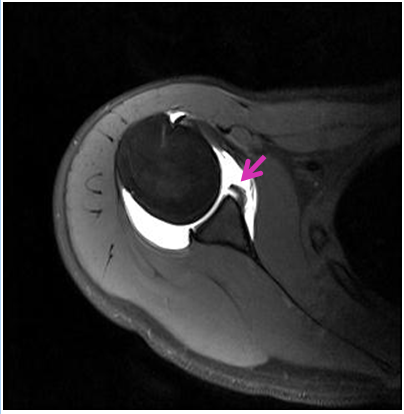

급성 탈구인 경우 진찰소견과 엑스레이 소견을 보고 탈구의 방향을 조사하는데 대부분의 경우 팔이 앞쪽으로 빠지는 전방 탈구입니다. 재발성 탈구가 되면 MRI 등으로 관절순 또는 인대들의 상태를 분석하는 것이 필요합니다. 또한 재발성 탈구시 골절을 동반하는 경우와 골결손이 심하면 수술전 CT사진이 필요합니다.

만성 불안정성의 경우 그 정도 및 종류에 따라 치료의 방법이 달라질 수 있으며 다방향 불안정성의 경우 혹은 전방 불안정성의 경우에도 그 정도가 심하지 않은 경우에는 물리 치료 등을 이용한 보존적 치료를 시행하여 볼 수 있으나, 반복적인 견관절의 전방 탈구 등이 지속될 때에는 수술적 치료가 필요합니다.수술적 치료의 방법은 관절이 탈구될 때 발생한 관절와순을 봉합하는 수술을 시행할 수 있으며 (일명 “방카르트수술”) 과거에는 관절을 열어 노출 시킨 후에 봉합하는 방법을 많이 이용하였으나 현재는 대부분 관절경을 이용하여 복원술을 시행하며 이로 인해 회복이 빠르고 수술 시 발생할 수 있는 관절 손상의 가능성이 줄었습니다. 골결손이 심한 경우에는 이에 대해 골이식 등의 치료법을 이용할 수 있습니다.